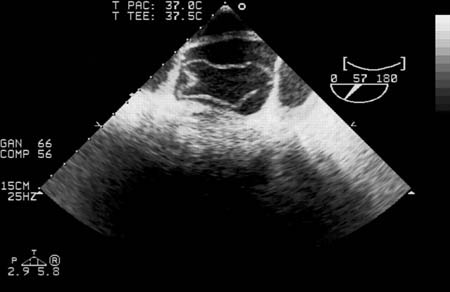

For type A dissections (ascending), transesophageal echocardiography may be done in the ICU or operating room to confirm the diagnosis and better evaluate the aortic valve.[11] Sensitivity and specificity are higher than for TTE.

If the patient presents with an incidental finding of chronic dissection (such as mediastinal widening or prominent aortic knob on chest x-ray), diagnosis is confirmed by cross-sectional imaging such as CTA, TTE, or MRI.[10][23][Figure caption and citation for the preceding image starts]: 3D CT, distal dissectionFrom the collection of Dr Eric E. Roselli; used with permission [Citation ends].3D CT, distal dissection[Figure caption and citation for the preceding image starts]: CT of a 71-year-old man showing type II dissecting aneurysm of the ascending aorta. Hematoma around the proximal segment of the ascending aorta (panels A-D) compressed the right pulmonary artery, almost occluding its patency and limiting the perfusion of the reciprocal lungStougiannos PN, Mytas DZ, Pyrgakis VN. The changing faces of aortic dissection: an unusual presentation mimicking pulmonary embolism. BMJ Case Reports 2009; doi:10.1136/bcr.2006.104414 [Citation ends].CT of a 71-year-old man showing type II dissecting aneurysm of the ascending aorta. Hematoma around the proximal segment of the ascending aorta (panels A-D) compressed the right pulmonary artery, almost occluding its patency and limiting the perfusion of the reciprocal lung​​​​​​ [Figure caption and citation for the preceding image starts]: Transesophageal echocardiography (transverse aortic section) showing a circumferential dissection of the ascending aorta in a 30-year-old patient with features of Marfan syndromeBouzas-Mosquera A, Solla-Buceta M, Fojón-Polanco S. Circumferential aortic dissection. BMJ Case Reports 2009; doi:10.1136/bcr.2007.049908 [Citation ends].Transesophageal echocardiography (transverse aortic section) showing a circumferential dissection of the ascending aorta in a 30-year-old patient with features of Marfan syndrome[Figure caption and citation for the preceding image starts]: CT scan showing dissecting aneurysm in a 45-year-old patient with Marfan syndrome experiencing chest painSanyal K, Sabanathan K. Chest pain in Marfan syndrome. BMJ Case Reports 2009; doi:10.1136/bcr.07.2008.0431 [Citation ends].CT scan showing dissecting aneurysm in a 45-year-old patient with Marfan syndrome experiencing chest pain